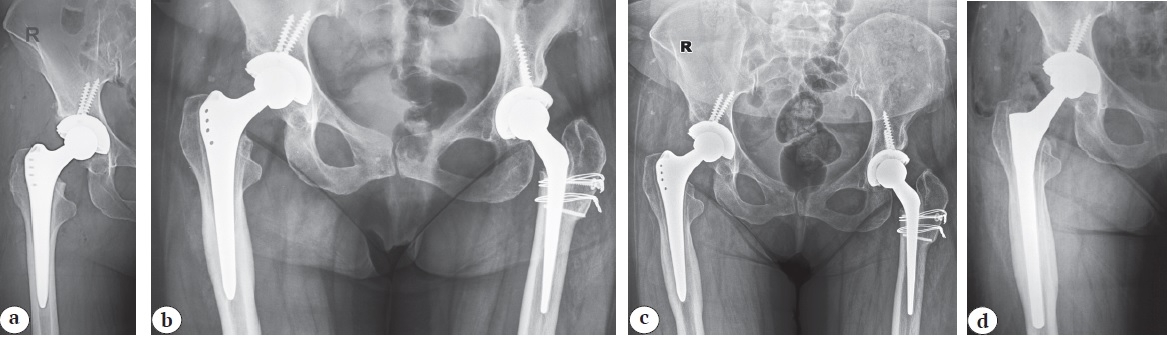

However, the presence of radiolucent lines may be a sign of gradual loosening of the femoral stem. Odds ratio for aseptic loosening of the Alloclassic stem in the presence of radiolucent lines is OR 12.178 (95% CI: 2.167-68.446; p = 0.003) (Fig. 6).

Fig. 6. A 49-year-old patient: bilateral hip dysplasia with high dislocation of the left hip (C2 according to Hartofilakidis) and low dislocation of the right hip (B2 according to Hartofilakidis). In June 2011, left THA was performed with a shortening osteotomy according to Paavilaainen. In March 2012, right THA was performed (a). On follow-up X-rays in February 2014, radiolucency lines are already detected in zones 1, 2, 6, and 7 of Gruen (b). However, until the beginning of 2020, there were no clinical manifestations of femoral component loosening. On X-rays in September 2020, the radiolucency lines became more pronounced (c), and the patient complained of hip pain after loading. Revision of the femoral component was performed (d)

On follow-up X-rays in February 2014, radiolucency lines are already detected in zones 1, 2, 6, and 7 of Gruen (b). However, until the beginning of 2020, there were no clinical manifestations of femoral component loosening. On X-rays in September 2020, the radiolucency lines became more pronounced (c), and the patient complained of hip pain after loading. Revision of the femoral component was performed (d)